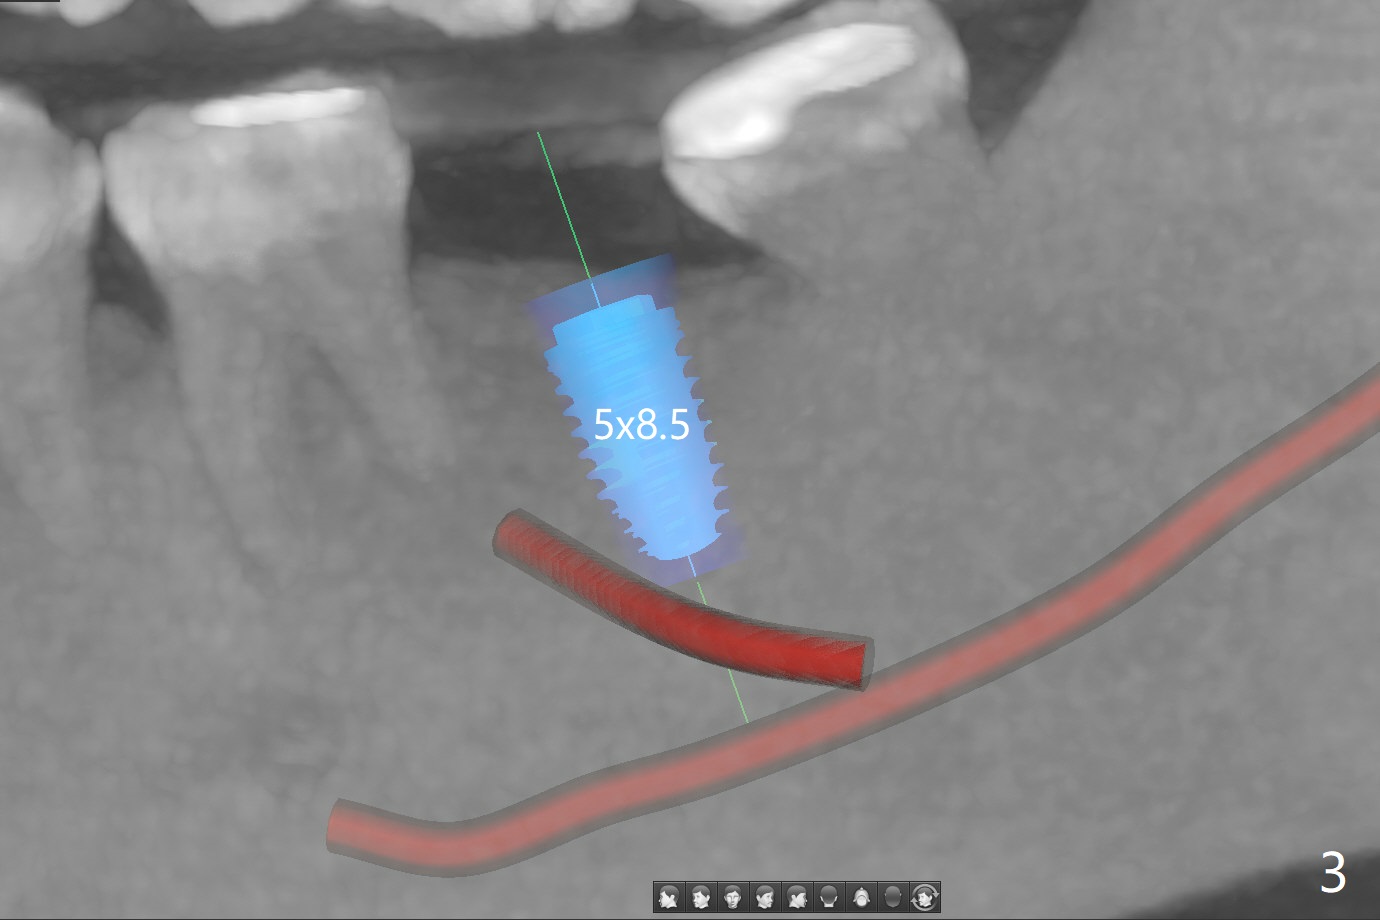

In contrast to #2 implant, the insertion torque of a 5x9 mm implant at #18 (Fig.1) is less than 10 Ncm because of depth difference between 2 implant systems. The design is for 5x10 mm. In fact each drill has its inherent 1.2 mm long tip. The 8.5 mm drilling depth is enough for 9 mm implant. The 2nd potential problem is that the implant may truncate a branch from the Inferior Alveolar Canal to the distal root of the 1st molar (Fig.2 (original design)). Ideally the implant should be placed distal and tilted mesial and short in length (Fig.3 (design to be improved)). A smaller implant may also help. A layer of new bone forms on the top of the implant 3 months postop (Fig.4 *). It is removed with surgical handpiece. After use of 5.6 mm profile drill, a 6x4 mm healing abutment is placed with minimal clearance from the mesial crest (Fig.5 *). A month later, a 5x4(3) mm pair abutment is seated apparently completely (Fig.6). A crown is delivered nearly 6.5 months postop (Fig.7 (mesial contact light)). The implant is subcrestal (*).